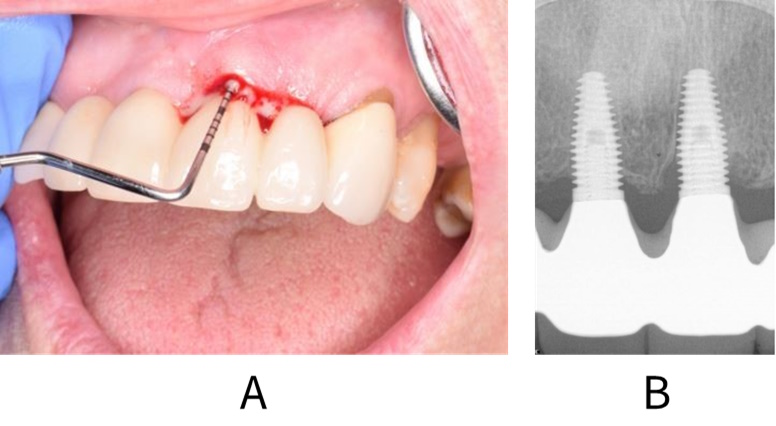

Peri-implantitis is defined as a pathological condition occurring in tissues around dental implants, characterized by inflammation in the peri-implant mucosa and progressive loss of supporting bone.114 The tissues will appear red and swollen, bleed on gentle palpation or probing and there may be suppuration (see figure: Peri-implantitis). Soft tissue inflammation is detected by probing (bleeding on probing indicates the presence of inflammation), while progressive bone loss is identified on radiographs. Recession of the surrounding mucosa can occur, exposing the implant threads. Peri-implantitis can progress rapidly. The patient may also experience pain around the implant. However, this usually only occurs during episodes of acute infection.

Clinical (A) and radiographic (B) images showing peri-implant inflammation and bone loss in a patient with peri-implantitis.